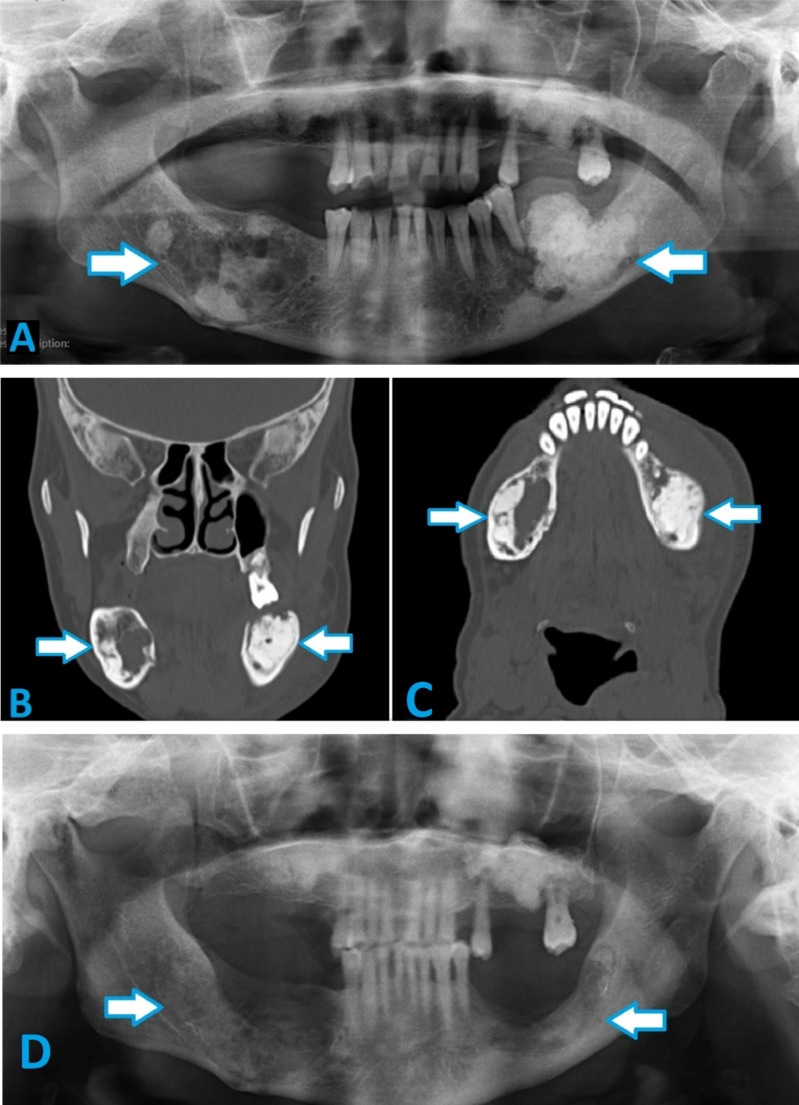

Abstract Image